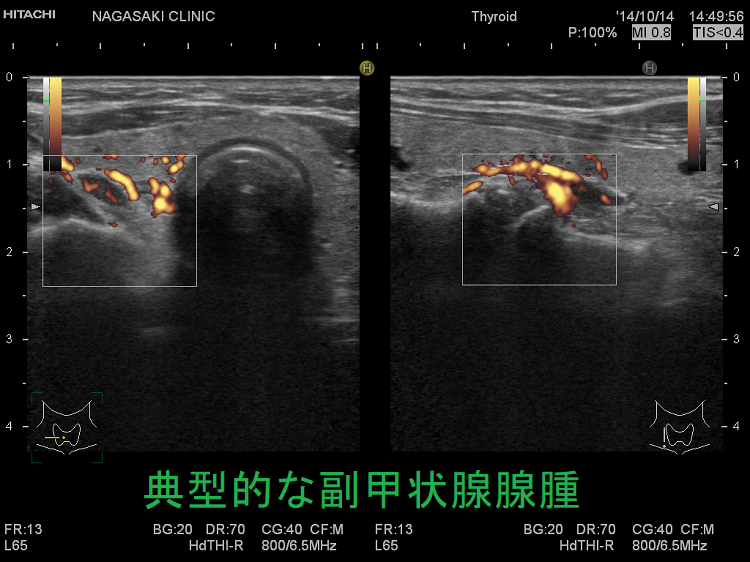

(➸)原因となる副甲状腺腺腫、副甲状腺癌、副甲状腺過形成をデジタルハイビジョン超音波診断装置で診断。エコーでは、甲状腺とのインピーダンスの違いにより、甲状腺-副甲状腺境界部に線状高エコーが生じます(右図の↓)。内部は中心血流を認め、リンパ節でないのが分かります。

ケース①

ケース② 右腕頭動脈分岐部上の副甲状腺腫